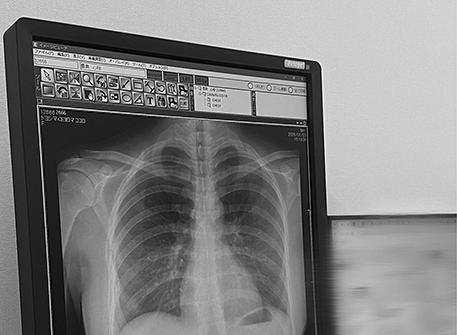

The incident began on 23/1 when Japanese model Kokoro Toyoshima, 22, posted a lung X-ray on social media platform X. Her brief accompanying message, "My lungs are very clear," was intended to update fans on her health, Oricon News reported.

However, the black-and-white image quickly went viral, garnering over 43 million views and 58,000 likes by 25/1. The primary draw was not the medical findings but the clear skeletal structure and body curves the X-ray revealed. Many viewers remarked on how unusual it was for an X-ray to so fully capture the subject's physique, particularly the idol's well-known H-cup chest.

Thousands of comments expressed surprise at the unusual image. "Even an X-ray exudes charm," one user remarked. Beyond the compliments on her appearance, some medically informed viewers also warned Toyoshima about mild scoliosis the X-ray revealed, advising her to adjust her posture to protect her health.

Orthopedic doctors state that a frontal chest X-ray is an effective tool for early detection of skeletal abnormalities, in addition to examining lung parenchyma, heart, and rib cage. A normal spine in a frontal X-ray appears as a straight line from the neck to the sacrum. If vertebrae are rotated or misaligned to the left or right, it signals scoliosis.